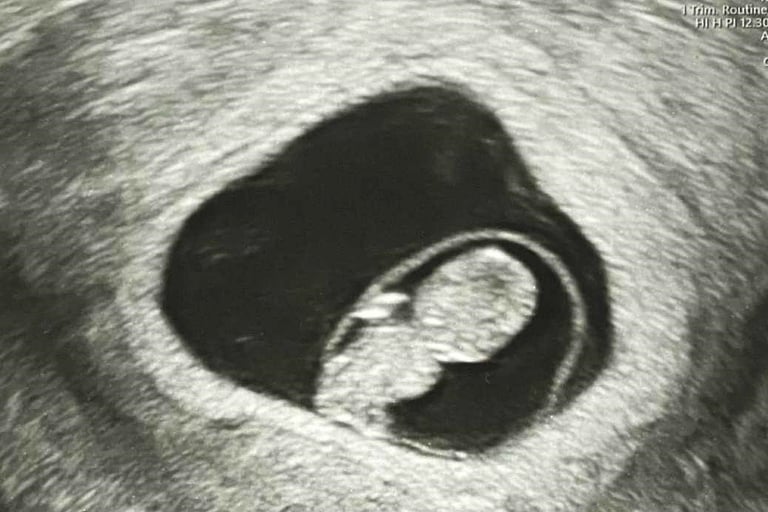

Today is probably one of the most memorable days of my life. I saw you for the first time. Yes, probably not in flesh and bones, but in a negative photo.

We had our first ultrasound today. The doctor took us into the room and told me to look at the screen. And there you were, a tiny human being sleeping peacefully in your mother’s womb. She then played your heartbeat. It was the most pleasant sound on earth. I didn’t even realize I was weeping. Thanks to Allah for blessing me with such a moment.

The doctor then checked your mother’s health and other reports, and everything seemed okay.

There you are, my tiny bundle of joy.